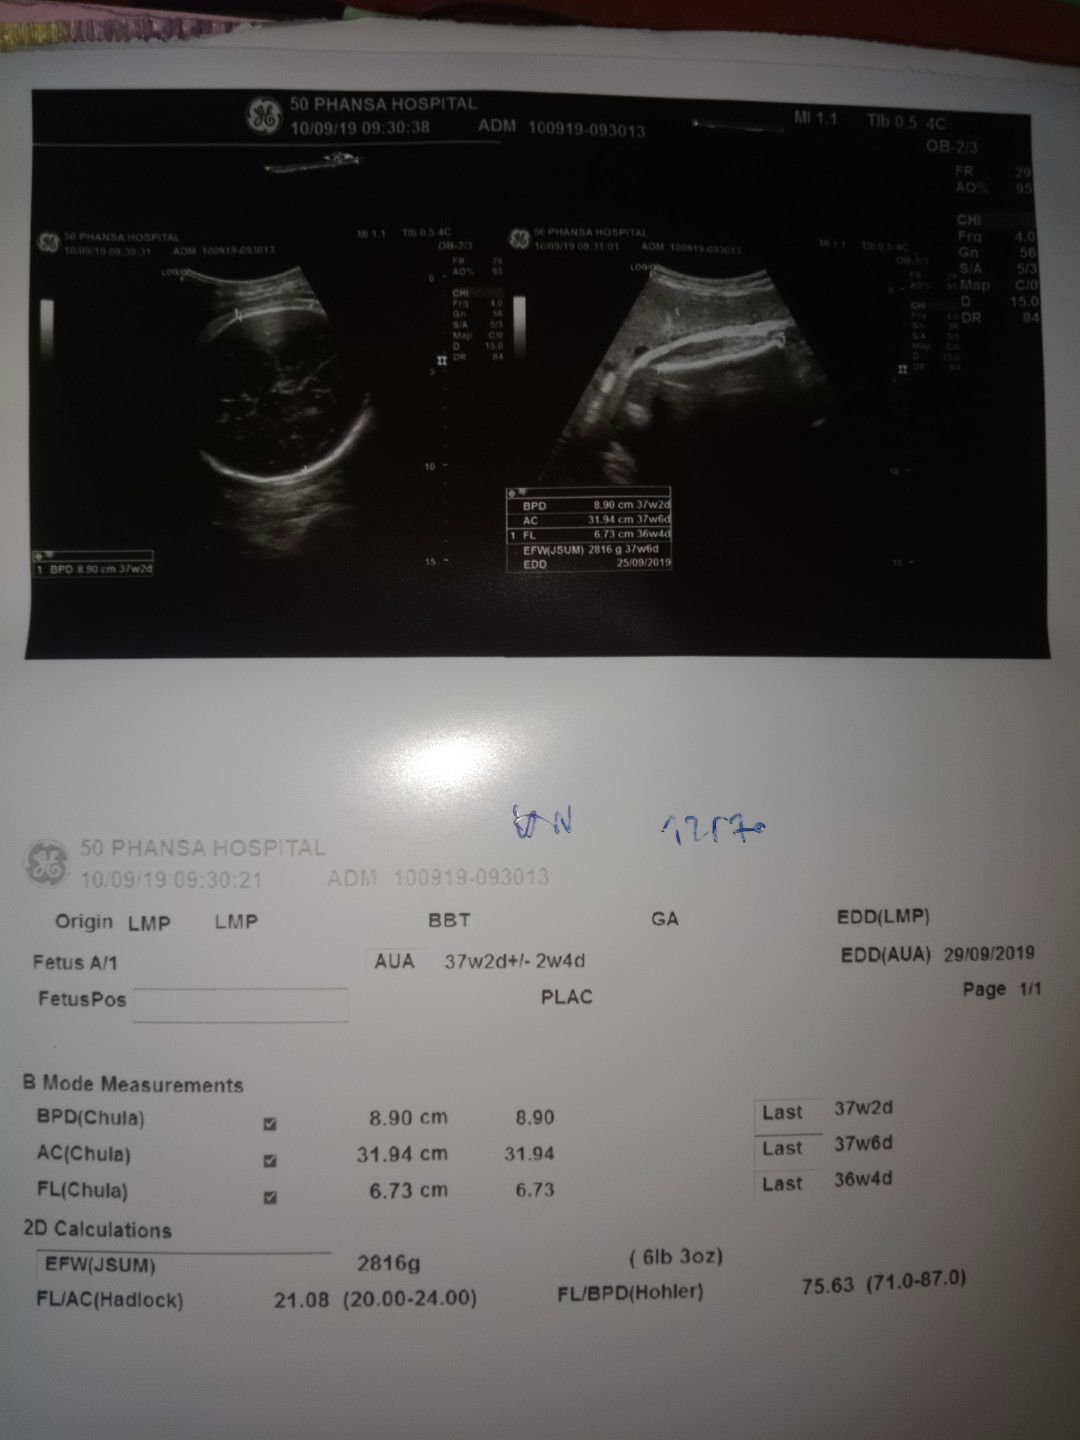

กำหนดที่แม่ฝากครั้งแรกวันที่เท่าไรค่ะ ยึดจากการซาวครั้งแรกเลยค่ะ